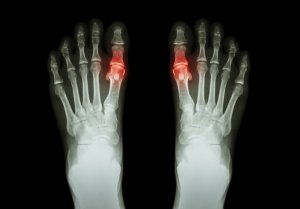

Подагра – це стан, викликаний накопиченням мікроскопічних кристалів сечової кислоти в суглобах. Ці кристали утворюють опуклості під шкірою або осідають в сечовивідних шляхах.

Однак коли це не спрацьовує, рівень сечової кислоти підвищується аномально. Утворюються кристали і осідають в суглобах, що веде за собою гострий біль.

- Спочатку може постраждати лише один або декілька суглобів. Це, як правило, великі пальці ноги, коліна або щиколотка. Цей біль може зникнути протягом декількох днів, але може повертатися час від часу.

- Як правило, уражений суглоб гарячий і червоний (запалюється). Взагалі, він стає чутливим і роздутим.

З іншого боку, у деяких людей може розвинутися хронічна подагра. Це може призвести до руйнування суглобів та втрати рухливості у певних суглобах.